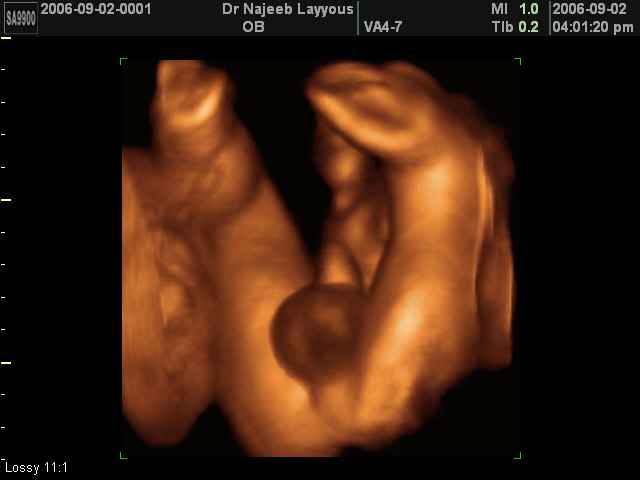

- 3D Photos échographie des parties du fœtus